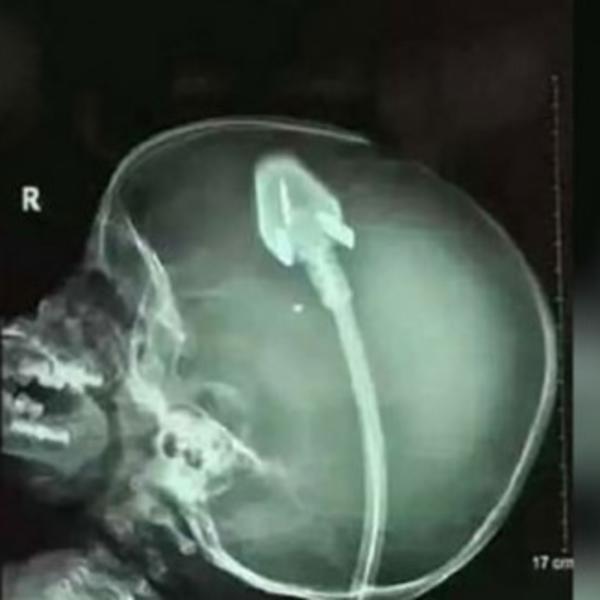

Tek su tada otkrili da malena pati od retkog oblika deformacije potkolenica koji se zove hemimela tibia.

- Reč je o relativno retkom poremećaju čiji je uzrok nepoznat, odnosno ne može se sa sigurnošću reći zašto se ta deca rađaju s defektima potkoleničnih kostiju. Lečenje je u samo određenom broju slučajeva uspešno i isključivo hirurško, ali čak ni to nema garancije. Naime, ponekad je i nakon svog truda i uloženog znanja prisutan neuspeh u lečenju i ne može se ništa učiniti. Tada je krajnja mera amputacija ekstremiteta nakon koje sledi protetso staramnje. To znači da mali pacijenti dobiju razne proteze i ortopedska pomagala - kazao je spec. ortoped i traumatolog dr. Milan Milošević iz Poliklinike Ribnjak.

- Poremećaj se odnosi samo na golenjičnu kost. Postoji više vrsta operacija, zavisno o kliničkoj slici pojedinca i dijagnostici. Pokušava sa raznim transferima koštano kožnih i mišićnih režnjeva nadomestiti tkivo koje nedostaje, no uvek je tu pitanje krvotoka odnosno vaskularizacije koja je ključna za život tkiva koje se prenosi. Ako nema dobrog dotoka krvi, tkivo odumire i operacija je neuspešna - kazao je dr. Milošević.

- Naišli smo na hirurga u SAD-u koji joj je hteo spasiti nogice i tvrdio je da je uradio puno takvih operacija. No Freja uopšte nije imala kosti u jednoj nozi, dok je u drugoj imala samo maleni fragment kosti. Čak nije bilo garancije da će to uspeti - nastavila je Danijel pojašnjavati svoje razloge.